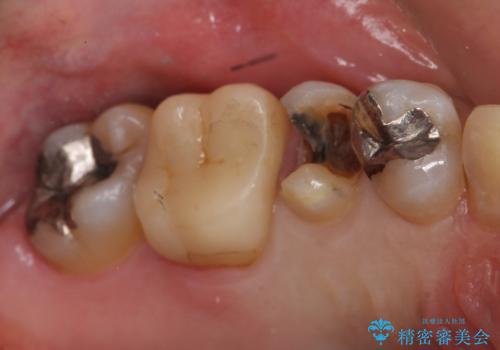

- 他院で矯正を終えた後、犬歯が尖っていることが気になるとのことで来院。

2番の欠損により3113の並びになっており、かつ、裏側はワイヤーで固定してありました。

特に右の犬歯と前歯の間には隙間が残っていました。(裏側のワイヤー固定の接着剤で一見隙間がなさそうにカモフラージュしてあります?が・・・)

その部分は汚れが非常にたまりやすくなっていました。

オールセラミッククラウンも選択肢としてあげられましたが、歯の表側のみを削るラミネートベニア修復を選択されました。

裏側の保定装置も外さずに済みました。